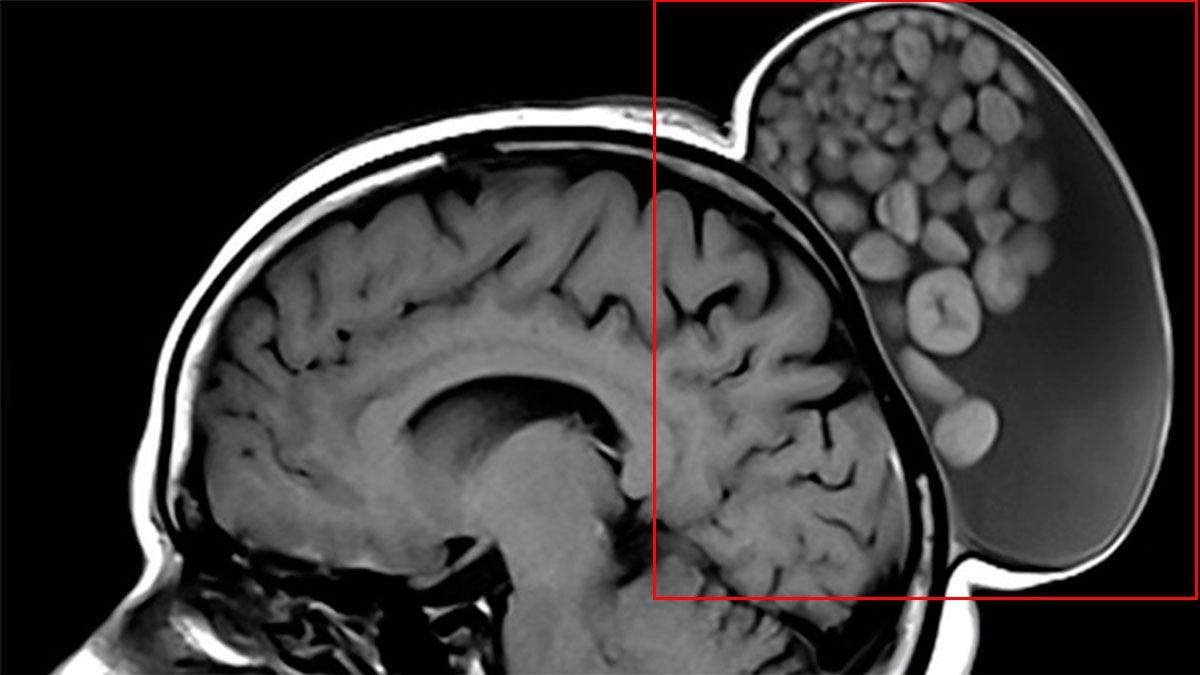

Un equipo médico dirigido por los neurocirujanos Sumit Thakar y Pavan Vasoya, del Instituto Sri Sathya Sai de Ciencias Médicas Superiores (India), extirparon un bulto en la cabeza de una mujer de 52 años que se encontraba lleno de bolas blancas como si fuese un "saco de canicas". En un informe publicado recientemente en la revista Radiology, los autores detallaron que la protuberancia estaba creciendo en el cuero cabelludo de la mujer desde su infancia.

Imagen de lo extraído Imagen de lo extraído

Después de completar la escisión quirúrgica, los doctores observaron que el quiste contenía material similar al sebo, esférulas duras y múltiples mechones de cabello flotando dentro de una matriz líquida. Un examen histopatológico confirmó el diagnóstico de un teratoma quístico maduro, con elementos de las tres capas germinales (embrionarios). Los especialistas controlaron la evolución de la mujer durante seis meses luego de la extracción del quiste y comprobaron que no se presentó una recurrencia.